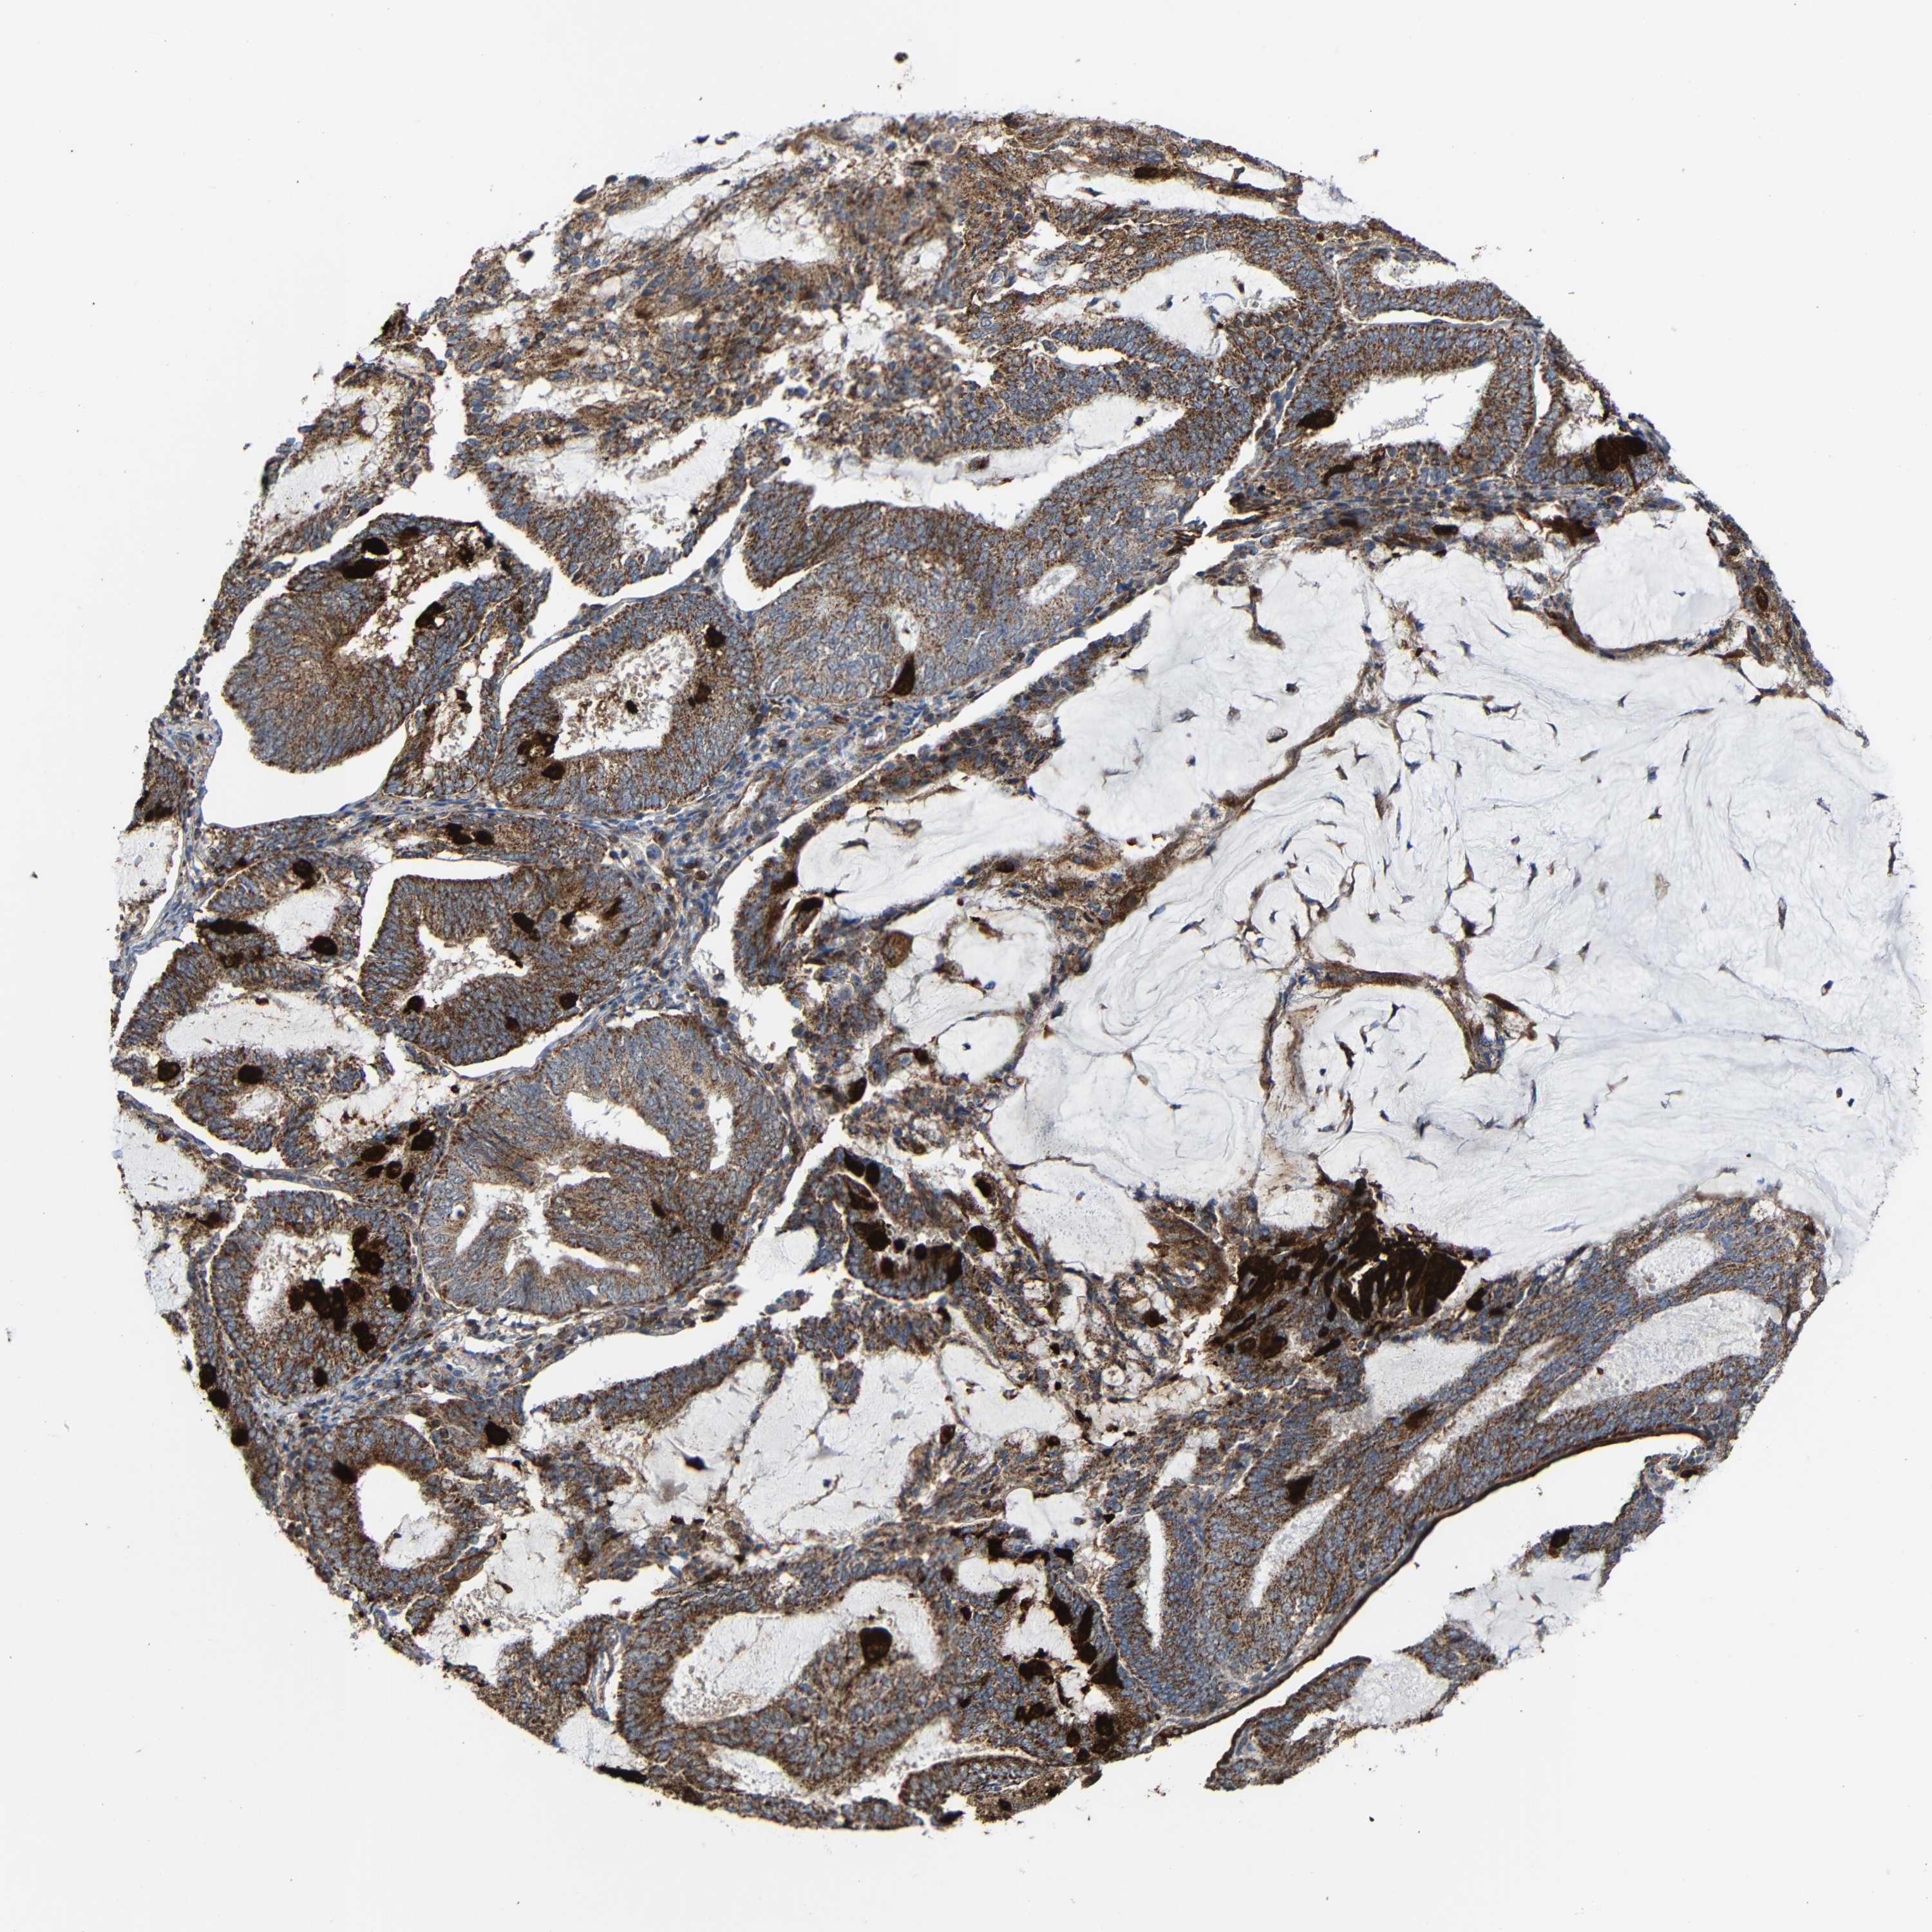

ENDOMETRIAL CANCER - Protein expressioni

A mouse-over function shows sample information and annotation data. Click on an image to view it in a full screen mode. Samples can be filtered based on level of antibody staining by selecting one or several of the following categories: high, medium, low and not detected. The assay and annotation is described here.

Note that samples used for immunohistochemistry by the Human Protein Atlas do not correspond to samples in the TCGA dataset.

Antibody stainingi

Antibody staining in the annotated cell types in the current human tissue is reported as not detected, low, medium, or high, based on conventional immunohistochemistry profiling in selected tissues. This score is based on the combination of the staining intensity and fraction of stained cells.

Each image is clickable and will lead to virtual microscopy that enables deeper exploration of all samples and also displays staining intensity scores, fraction scores and subcellular localization as well as patient and tissue information for each sample.

Antibody HPA011294

Antibody HPA012819

Staining

High

Medium

Low

Not detected

Intensity

Strong

Moderate

Weak

Negative

Quantity

>75%

75%-25%

<25%

None

Location

Nuclear

Cytoplasmic/membranous

Cytoplasmic/membranous,nuclear

Adenocarcinoma, NOS